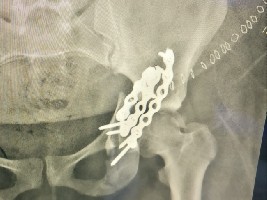

وأضافت أن «الندوة شهدت إعلان نتائج تقرير التسجيل السرطاني العراقي لعام 2024، وعرض التقييم السنوي لبرنامج الكشف المبكر عن السرطان لعام 2025، إلى جانب محاضرة علمية قدمتها، مديرة شعبة الوقاية والسيطرة المبكرة على أمراض السرطان في مجلس السرطان سرى ياسين عبد، حول استراتيجية السيطرة على السرطان في العراق للأعوام (2026–2030)، ودور برامج الكشف المبكر في تقليل نسب الإصابة، وتحسين فرص الشفاء، والارتقاء بمستوى الرعاية الصحية المقدمة للمواطنين». وأكد الحسناوي خلال الندوة، بحسب البيان، أن «الوزارة حققت تقدماً مهماً في تطوير خدمات علاج الأورام، من خلال توفير مراكز العلاج الشعاعي في جميع المحافظات لأول مرة، وتنفيذ حملات توعوية وطنية للكشف المبكر عن السرطان، ولا سيما سرطان الثدي، بالتعاون مع مجلس السرطان ودائرة الأمور الفنية والشركة العامة لتسويق الأدوية ودائرة الصحة العامة».